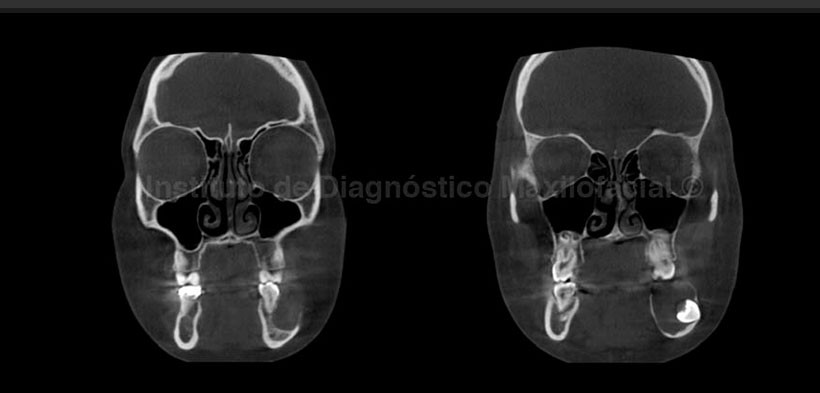

La tomografía computarizada de haz cónico (cone beam), en los cortes axial, coronal, y reconstrucción 3D; nos muestra el desplazamiento, adelgazamiento y erosión de las tablas óseas vestibular y lingual. Se aprecia también la estrecha relación de la pieza 37 con la tabla ósea vestibular y se confirma también el desplazamiento caudal del conducto dentario inferior (Fig. 2, 3 y 4).